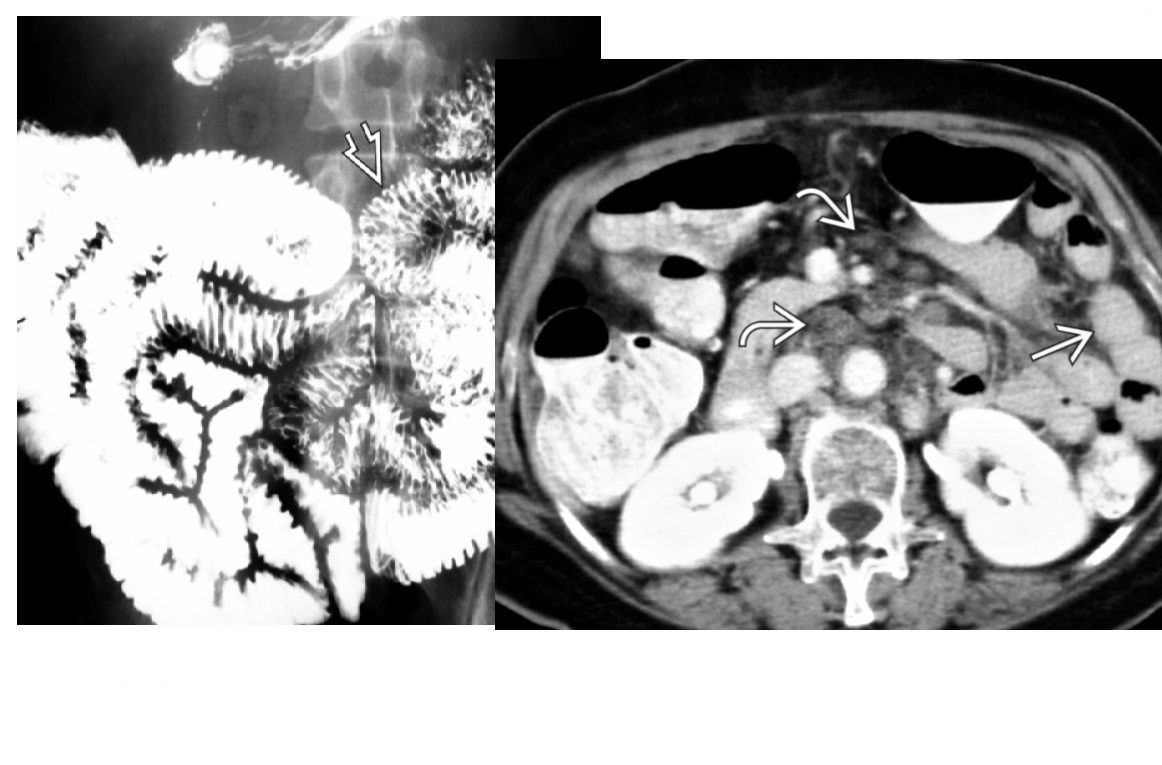

Carcinoid

spiculated mesenteric mass with calcification/ desmoplastic reaction

Tethering of SB loops

90% arise in terminal ileum/appendix

Hyper-vascular liver mets - Carcinoid syndrome

111I- Octreotide scans (1st - highest sensitivity)

or 123I-MIBG (for 10% dont take up octreotide)

for Dx and staging

Big centres use gallium PET

Assocaited with MEN 1 or MEN 2a

DDX

Sclerosing mesenteritis/ mesenteric pannicultuis

- FAT HALO sign - Mass envelop vessels, but preservation of fat around vessels

- usually jejunal small bowel mesentery

Gastrointestinal Stromal Tumor (GIST)

- Hypervascular tumor, not associated with desmoplastic effect on mesentery

Small Bowel Carcinoma

- More common in duodenum or jejunum than in ileum

- Causes luminal obstruction

- Mass and metastases are hypovascular